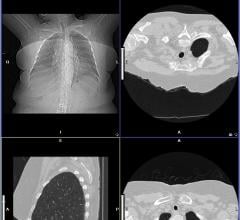

Imaging is critical to all medical specialties so it is logical that images should be available to specialists outside of radiology. There is a trend to reduce repeat exams by making images more easily accessible, including prior exams. This traditionally has been accomplished using the cumbersome process of mailing or physically carrying CDs to referring physicians. Often these CDs do not open or take a long time to download. Stage 2 Meaningful Use requirements for certified electronic medical records (EMR) also call for the sharing of medical images electronically to help improve efficiency and reduce healthcare costs. All of these factors have given rise to remote image access systems.

Today’s digital picture archiving and communication systems (PACS) is highlighted with several choice words around the industry: accessible, flexible, Web-based, thin client versus thick client and vendor-neutral. Whatever term is used to describe the PACS of today and the future, one thing is clear: the aim now is to be able to store medical images, sourced from any modality, in a secure location on a network and retrieve them for review from any platform or any device.

Several industries have used cloud solutions for many years, but cloud computing only recently started to be used in healthcare. According to the National Institute of Standards and Technology (NIST), cloud computing is defined as “a model for enabling convenient, on-demand network access to a shared pool of configurable computing resources (e.g., networks, servers, storage, applications and services) that can be rapidly provisioned and released with minimal management effort or service provider interaction.”1 As more and more healthcare organizations (HCOs) adopt electronic medical records (EMRs), the cloud database has offered an efficient solution for image sharing, particularly in radiology where it is bridging the gap between referring physicians and radiologists.